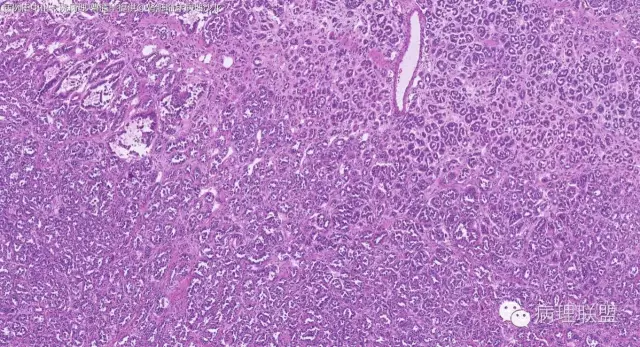

女性,50岁,肾上腺肿物(影像及手术均确认肿物位于肾上腺,界限清楚)。血压升高。(病例由 中山一院病理 曹清华提供,致谢!)

病例讨论

中山一院病理 曹清华

CK,Vimentin,CD56 阳性

inhibina, melana, syn, cga, wt-1, cd57均阴性

伴假腺样结构的肾上腺皮质腺瘤,合并髓脂肪瘤

从肿瘤的位置及镜下与肾上腺皮质的关系看,应该像是皮质来源肿瘤。假腺样结构的皮质腺瘤没有见过,似乎文献也还没查到。另外inhibina, melanA, syn均阴性(肿瘤旁正常皮质阳)感觉有点迷惑。。。请老师指教,有相关文献么?@武警嘉兴医院 周泉